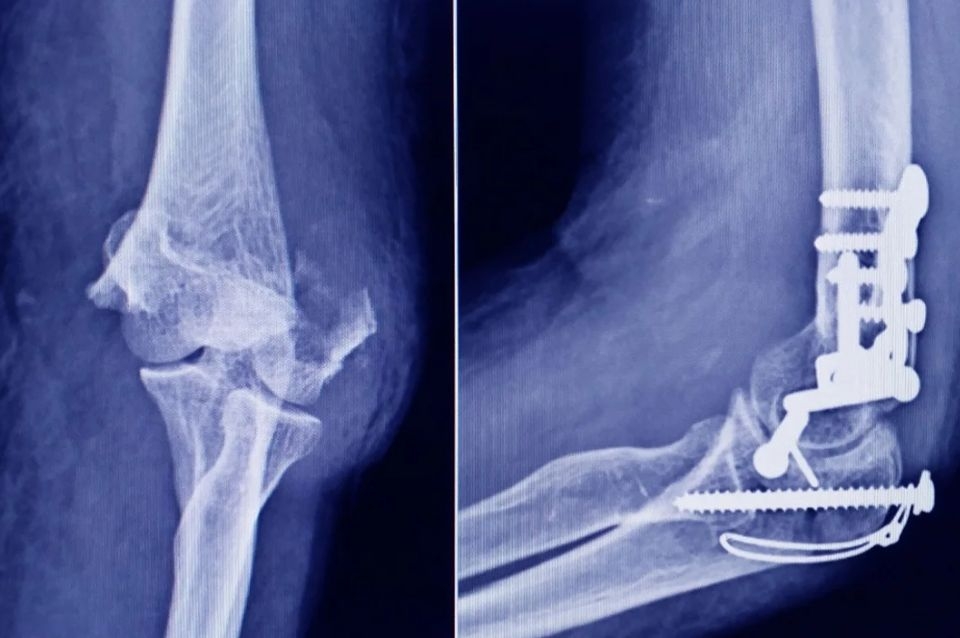

Se trata de un tornillo utilizado en cirugías traumatológicas que fue detectado durante una inspección de control de mercado realizada en una ortopedia ubicada en la ciudad de San Miguel de Tucumán.

Las autoridades de la ANMAT dieron a conocer las características del producto para su advertencia: STRYKER 10 mm X 28 mm - BIOABSORBABLE - ACL INTERFERENCE SCREW - REF 234-010-067 - LOT 90905.